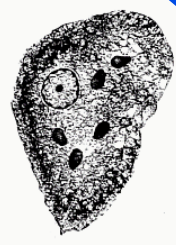

Entamoeba coli (cyst)

Entamoeba coli (cyst)